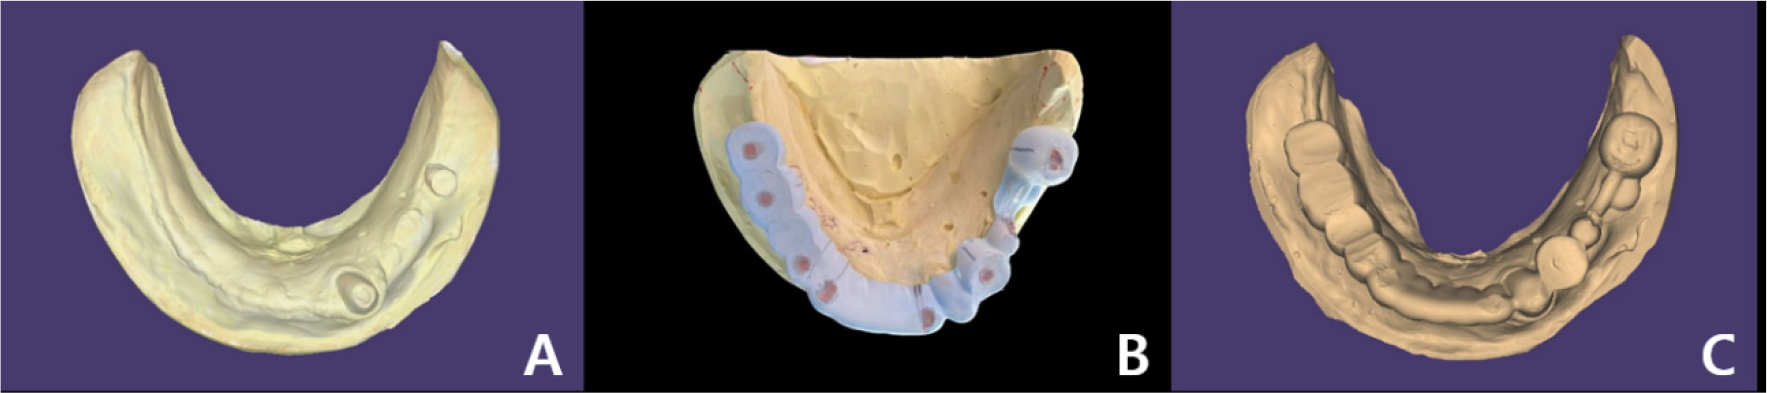

A 58-year-old male patient visited our hospital with chief complaints of missing mandibular teeth. The patient had hypertension and hyperlipidemia. Clinical and radiological examinations revealed multiple tooth loss in the mandible and canting of the maxillary teeth. The implant in the lower left second premolar area showed degree II mobility and vertical bone loss around the fixture, indicating a loss of osseointegration (Figs. 1 and 2). After removal of the dental implant on #35, implant placement was planned at sites #47, 46, 44, 43, 32, 33, 34, 36, and 37. The patient refused to undergo temporary denture placement. A radiographic stent was fabricated after bite registration using a record base, which is the conventional method for fabricating a stent in a partially edentulous jaw. CBCT was taken, and the stone model was scanned using an optical scanner (Medit T500 Dental 3D Scanner; Medit Corp., Seoul, Korea) (Fig. 3A).

The model and CT scan data were superimposed using a dedicated software (DentiqGuide; 3D Industrial Imaging Co., Ltd., Seoul, Korea) for guided surgery and treatment planning. However, the mandibular arch had one tooth and one healing abutment on one side, which was not properly superimposed. Based on previous experience, it was thought that superimposition would be possible with 2-3 remaining teeth; therefore, the part where additional radiographic markers were not attached became a problem. To solve this problem, after applying powder (VITA powder scan spray; VITA Zahnfabrik H. Rauter GmbH & Co., KG, Bad Säckingen, Germany) to the radiographic stent and placing it on the stone model, an optical scan was performed to create another STL file (Fig. 3B and 3C).

DentalCAD 2.3 (Exocad GmbH; Darmstadt, Germany) program was used to superimpose radiographic stent model scan data with model scan data, and then both files were loaded on DentiqGuide software. DICOM files from CBCT data and radiographic stent model scan data were superimposed on DentiqGuide software using gutta-percha (Temporary stopping; GC Corporation, Tokyo, Japan) to match the model scan data with CBCT data (Fig. 4). In addition, to confirm that the model scan data and CBCT data matched accurately, we checked whether the gingiva line of the model and the bone line of CBCT matched the software and whether the location of the gutta-percha in the model and CBCT matched (Fig. 5). Implant planning and surgical guide design were performed by referring to the CBCT and model scan data, and the surgical guide was printed using a DLP (Digital Light Processing) type 3D printer (Zenith D; Dentis, Daegu, Korea) (Fig. 6). The lower left canine root is tilted mesially. Therefore, when working with the planning software, placing the implant on the adjacent lateral incisor was difficult, and the cantilever was planned after placement on the central incisor.